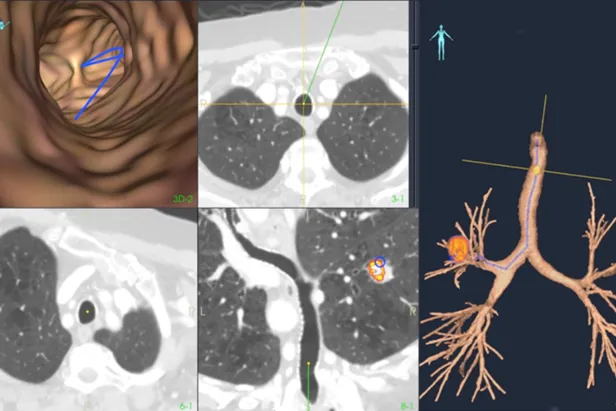

Lunge og bronkoskopi

Lungekreft er den kreftformen med høyest forekomst og dødelighet både i Norge og internasjonalt. Tidlig og presis diagnostikk er avgjørende for overlevelse. Tradisjonelt brukes fleksible videobronkoskop til visuell undersøkelse og biopsi, men metoden har begrensninger når svulster sitter perifert i lungene og ikke er synlige i luftveiene. For å møte denne utfordringen forsker MiDT på avanserte navigasjonsteknologier som kombinerer preoperative CT-bilder med sanntids elektromagnetisk posisjonssporing under bronkoskopi. Dette gir bedre tilgang til små og vanskelig tilgjengelige lesjoner, og kan øke treffsikkerheten ved prøvetaking og behandling. Prosjektene utvikles i tett samarbeid mellom klinikere, teknologer og industripartnere, med mål om å redusere risiko, forbedre pasientbehandling og legge grunnlag for mer persontilpasset diagnostikk.